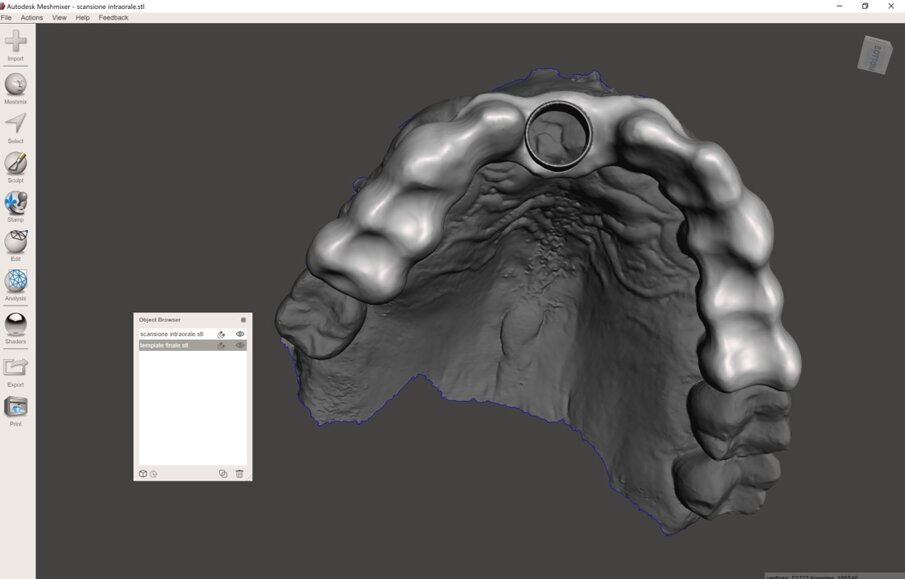

I dati Digital Imaging and Communication in Medicine (DICOM) derivanti dalla CBCT, insieme con il file standard tesselletion language (.STL) ottenuto tramite la scansione intraorale, venivano quindi caricati in cloud in un software di Intelligenza Artificiale (Virtual Patient Creator, RELU). Tali dati venivano elaborati e il software di Intelligenza Artificiale restituiva, in meno di 10 minuti, la ricostruzione 3D della maxilla del paziente, ottenuta tramite segmentazione ossea automatica, accoppiata e allineata alla scansione intraorale (Fig. 4). Il software, inoltre, restituiva la segmentazione di ciascun singolo elemento dentario, sotto forma di files .STL separati, nei quali la corona veniva direttamente dalla scansione intraorale, mentre la radice dalla CBCT (Fig. 5). La “fusione” automatica del dato della CBCT con quello della scansione intraorale, e il perfetto allineamento tra le strutture anatomiche, rappresentava il risultato dell’applicazione dell’Intelligenza Artificiale. La stessa area rigenerata veniva opportunamente segmentata (Fig. 6). A questo punto, l’operatore era in grado di visualizzare tutte le strutture, selezionare quelle interessanti ed esportarle come files .STL. Tali files venivano quindi caricati all’interno di una applicazione dedicata per l’uso per la realtà aumentata (Holodentist, Fifthingenium), insieme con la libreria implantare del sistema scelto (Naturactis, Lyra ETK) per la risoluzione dello specifico caso clinico (Fig. 7). L’operatore vestiva quindi gli occhialini per la Realtà Aumentata (MagicLeap2, Magic Leap) e, anche attraverso l’aiuto di uno specifico joypad, era in grado di pianificare l’impianto in 3D nell’esatta posizione, profondità ed inclinazione, impiegando gli ologrammi (Clicca QUI). Terminata la pianificazione e salvata la posizione dell’impianto, essa veniva esportata e impiegata per disegnare, all’interno di software open-source, un template per una chirurgia guidata statica (Figg. 8, 9). Dal momento che Intelligenza Artificiale e Realtà Aumentata non possiedono ancora le certificazioni per l’impiego clinico, tutti i files erano quindi re-importati all’interno di software radiologico certificato (MIMICS, Materialise) per il controllo della posizione implantare nelle cross-sections radiologiche (Figg. 10, 11).

Fig. 8_Disegno della dima chirurgica con software open-source (Meshmixer, Autodesk), visione occlusale.